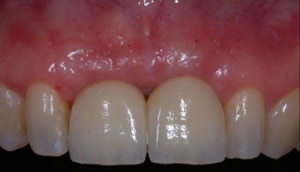

C'est la position spatiale de l'implant qui détermine la qualité de la prothèse en terme fonctionnel, esthétique.

Photos extraites du diaporama :